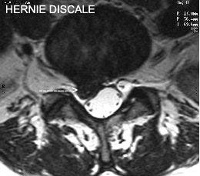

Hernie Discale

Coupe IRM

Les vertèbres lombaires (L1 à L5) et le sacrum (S1) sont séparées par les disques intervertébraux qui jouent un rôle d'amortisseur. Le disque est formé à sa périphérie d'un manchon fibreux (annulus) résistant et élastique qui maintient la cohésion des vertèbres et en son centre d'un noyau gélatineux (nucléus).

Un ligament épais et solide, le ligament vertébral commun postérieur, parcourt l'arrière des corps vertébraux et des disques. Il contribue à la cohésion des vertèbres lors des mouvements et maintient le disque en arrière.

Le canal rachidien est l'orifice situé derrière les corps vertébraux et les disques, et entre les articulaires postérieures. Il contient les racines des nerfs qui proviennent de la moelle épinière et qui se dirigent vers le bas du corps. La moelle épinière se termine au niveau des dernières vertèbres dorsales, au niveau lombaire le canal rachidien ne contient donc que des nerfs qui forment la « queue de cheval ».

Le nerf sciatique est formé par la réunion de deux racines nerveuses, L5 et S1. Ces dernières sortent du canal vertébral en passant derrière les disques.